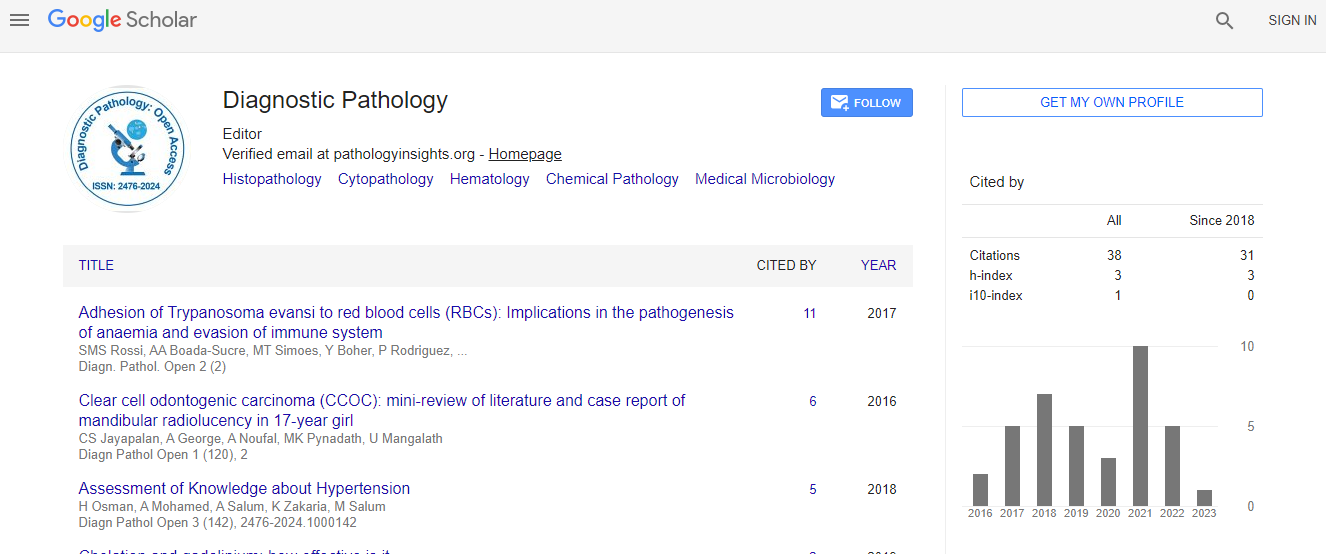

Diagnostic Pathology

Diagnostic Pathology: Open Access- Open Access Journals